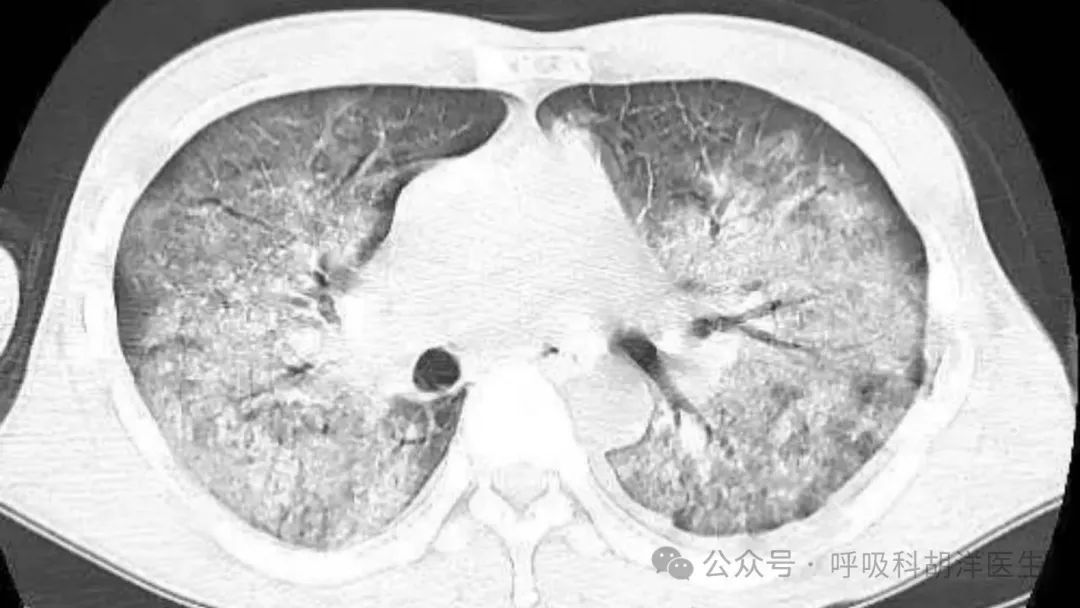

当时用的烤油膏应该是三无产品。烤油的时候头皮疼。烤油后,当时没有反应。回家后第三天,我开始肩膀和背部出现大块皮疹。我去当地医院打了一针。皮疹退去后不久,就出现了咳嗽症状。干咳是主要症状,逐渐加重,出现哮喘。白肺表现已经出现在当地的CT检查中。虽然用了很多好药,但是病情还是逐渐加重。虽然来找我的时候看上去病情比较轻微,但实际上是因为她身体很好,还能坚持走路,住下后很快就会呼吸衰竭。